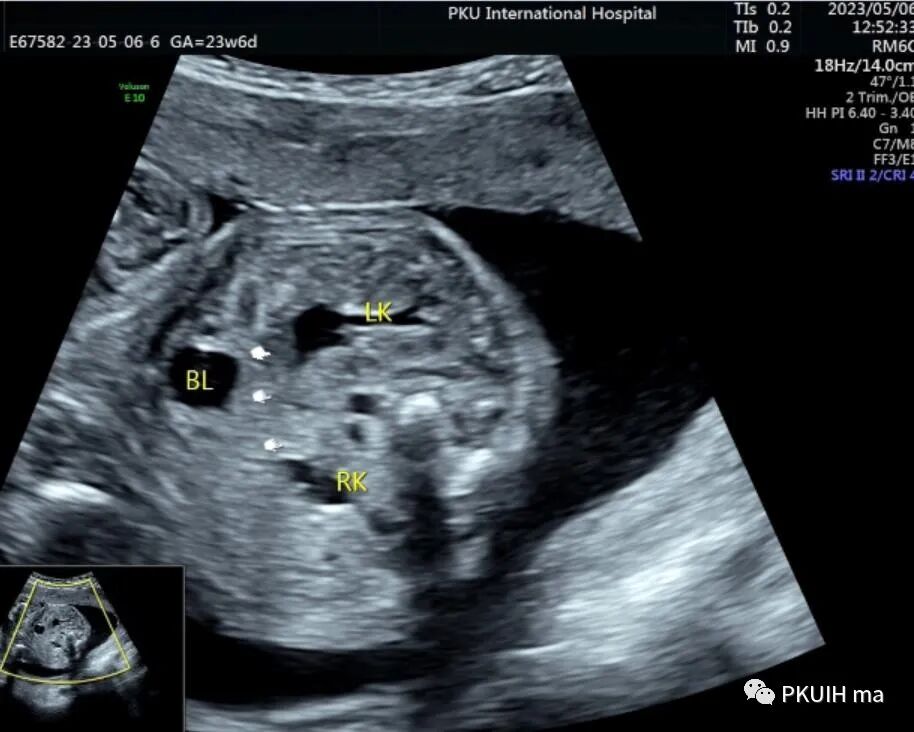

双肾横断面观察双肾盂轻微分离,肾门指向腹侧,呈倒“八”字征。(LK:左肾,RK:右肾)

仔细观察双肾下极越过腹主动脉于腹主动脉和下腔静脉的前方相融合,同时肾的位置相对低,下极接近胎儿膀胱。(DAO:降主动脉,IVC:下腔静脉,BL:膀胱)